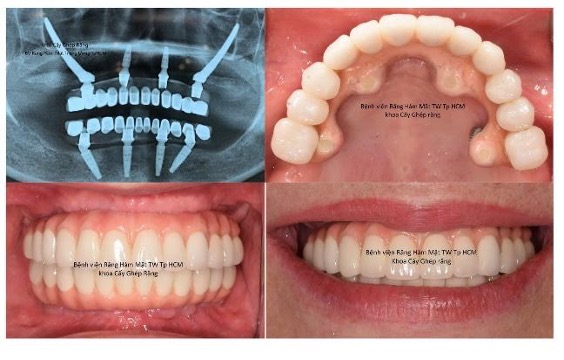

Phân khoa Cấy ghép răng, trực thuộc khoa Phẫu Thuật Hàm Mặt, được Viện thành lập vào tháng 5/1999. Khoa Cấy ghép răng chính thức được Bộ Y t ế công nhận vào năm 2004. Nguyên Viện trưởng, PGS. TS. Lâm Ngọc Ấn cùng với các Bác sĩ nước ngoài đã thực hiện ca implant đầu tiên tại Việt Nam ngày 10/1/1994, đến nay, sau 26 năm vẫn còn sử dụng tốt. Hiện nay khoa thực hiện được hầu hết các kỹ thuật trong implant như Nâng xoang, các kỹ thuật tăng thể tích xương và mô mềm, đặt implant xương gò má, phẫu thuật dời dây thần kinh răng dưới, phục hình dưới sự hỗ trợ của kỹ thuật số… nhờ đó khoa có thể giải quyết được hầu hết các trường hợp lâm sàng từ đơn giản đến phức tạp.

Ghép xương tự thân

Phục hình trên bệnh nhân cắt đoạn xương hàm và ghép xương tự thân